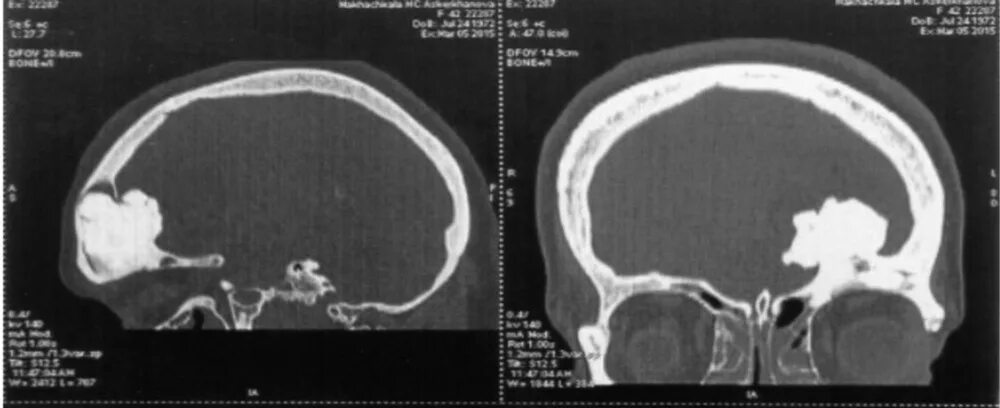

Остеома мрт